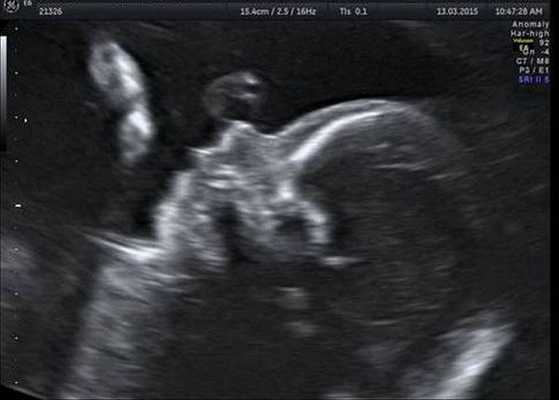

Как правило, диагностировать синдром Гольденхара не составляет труда. Постановка этого диагноза основана на оценке внешних признаков, клинической симптоматике и результатах дополнительных исследований — КТ, рентгенографии, МСКТ черепа, эхокардиографии и ультразвуковой диагностики. КТ, как правило, проводится для подготовки ребёнка к оперативному лечению.

Генетическое тестирование может быть предложено для подтверждения диагноза, т. е. для исключения генетических состояний, включающих аналогичные лицевые аномалии, связанные с хромосомными и моногенными нарушениями. К таким заболеваниям относятся прогрессирующая гемиатрофия лица, синдром Нагера, челюстно-лицевой дизостоз и др. Однако минимальные диагностические критерии не установлены. Имеются описания единичных случаев диагностики данного синдрома с помощью тестирования до родов.

Индивидуальная профилактика синдрома предполагает проведение медико-генетического консультирования семьи и пренатальной ультразвуковой диагностики беременной женщины в установленные сроки [12] .